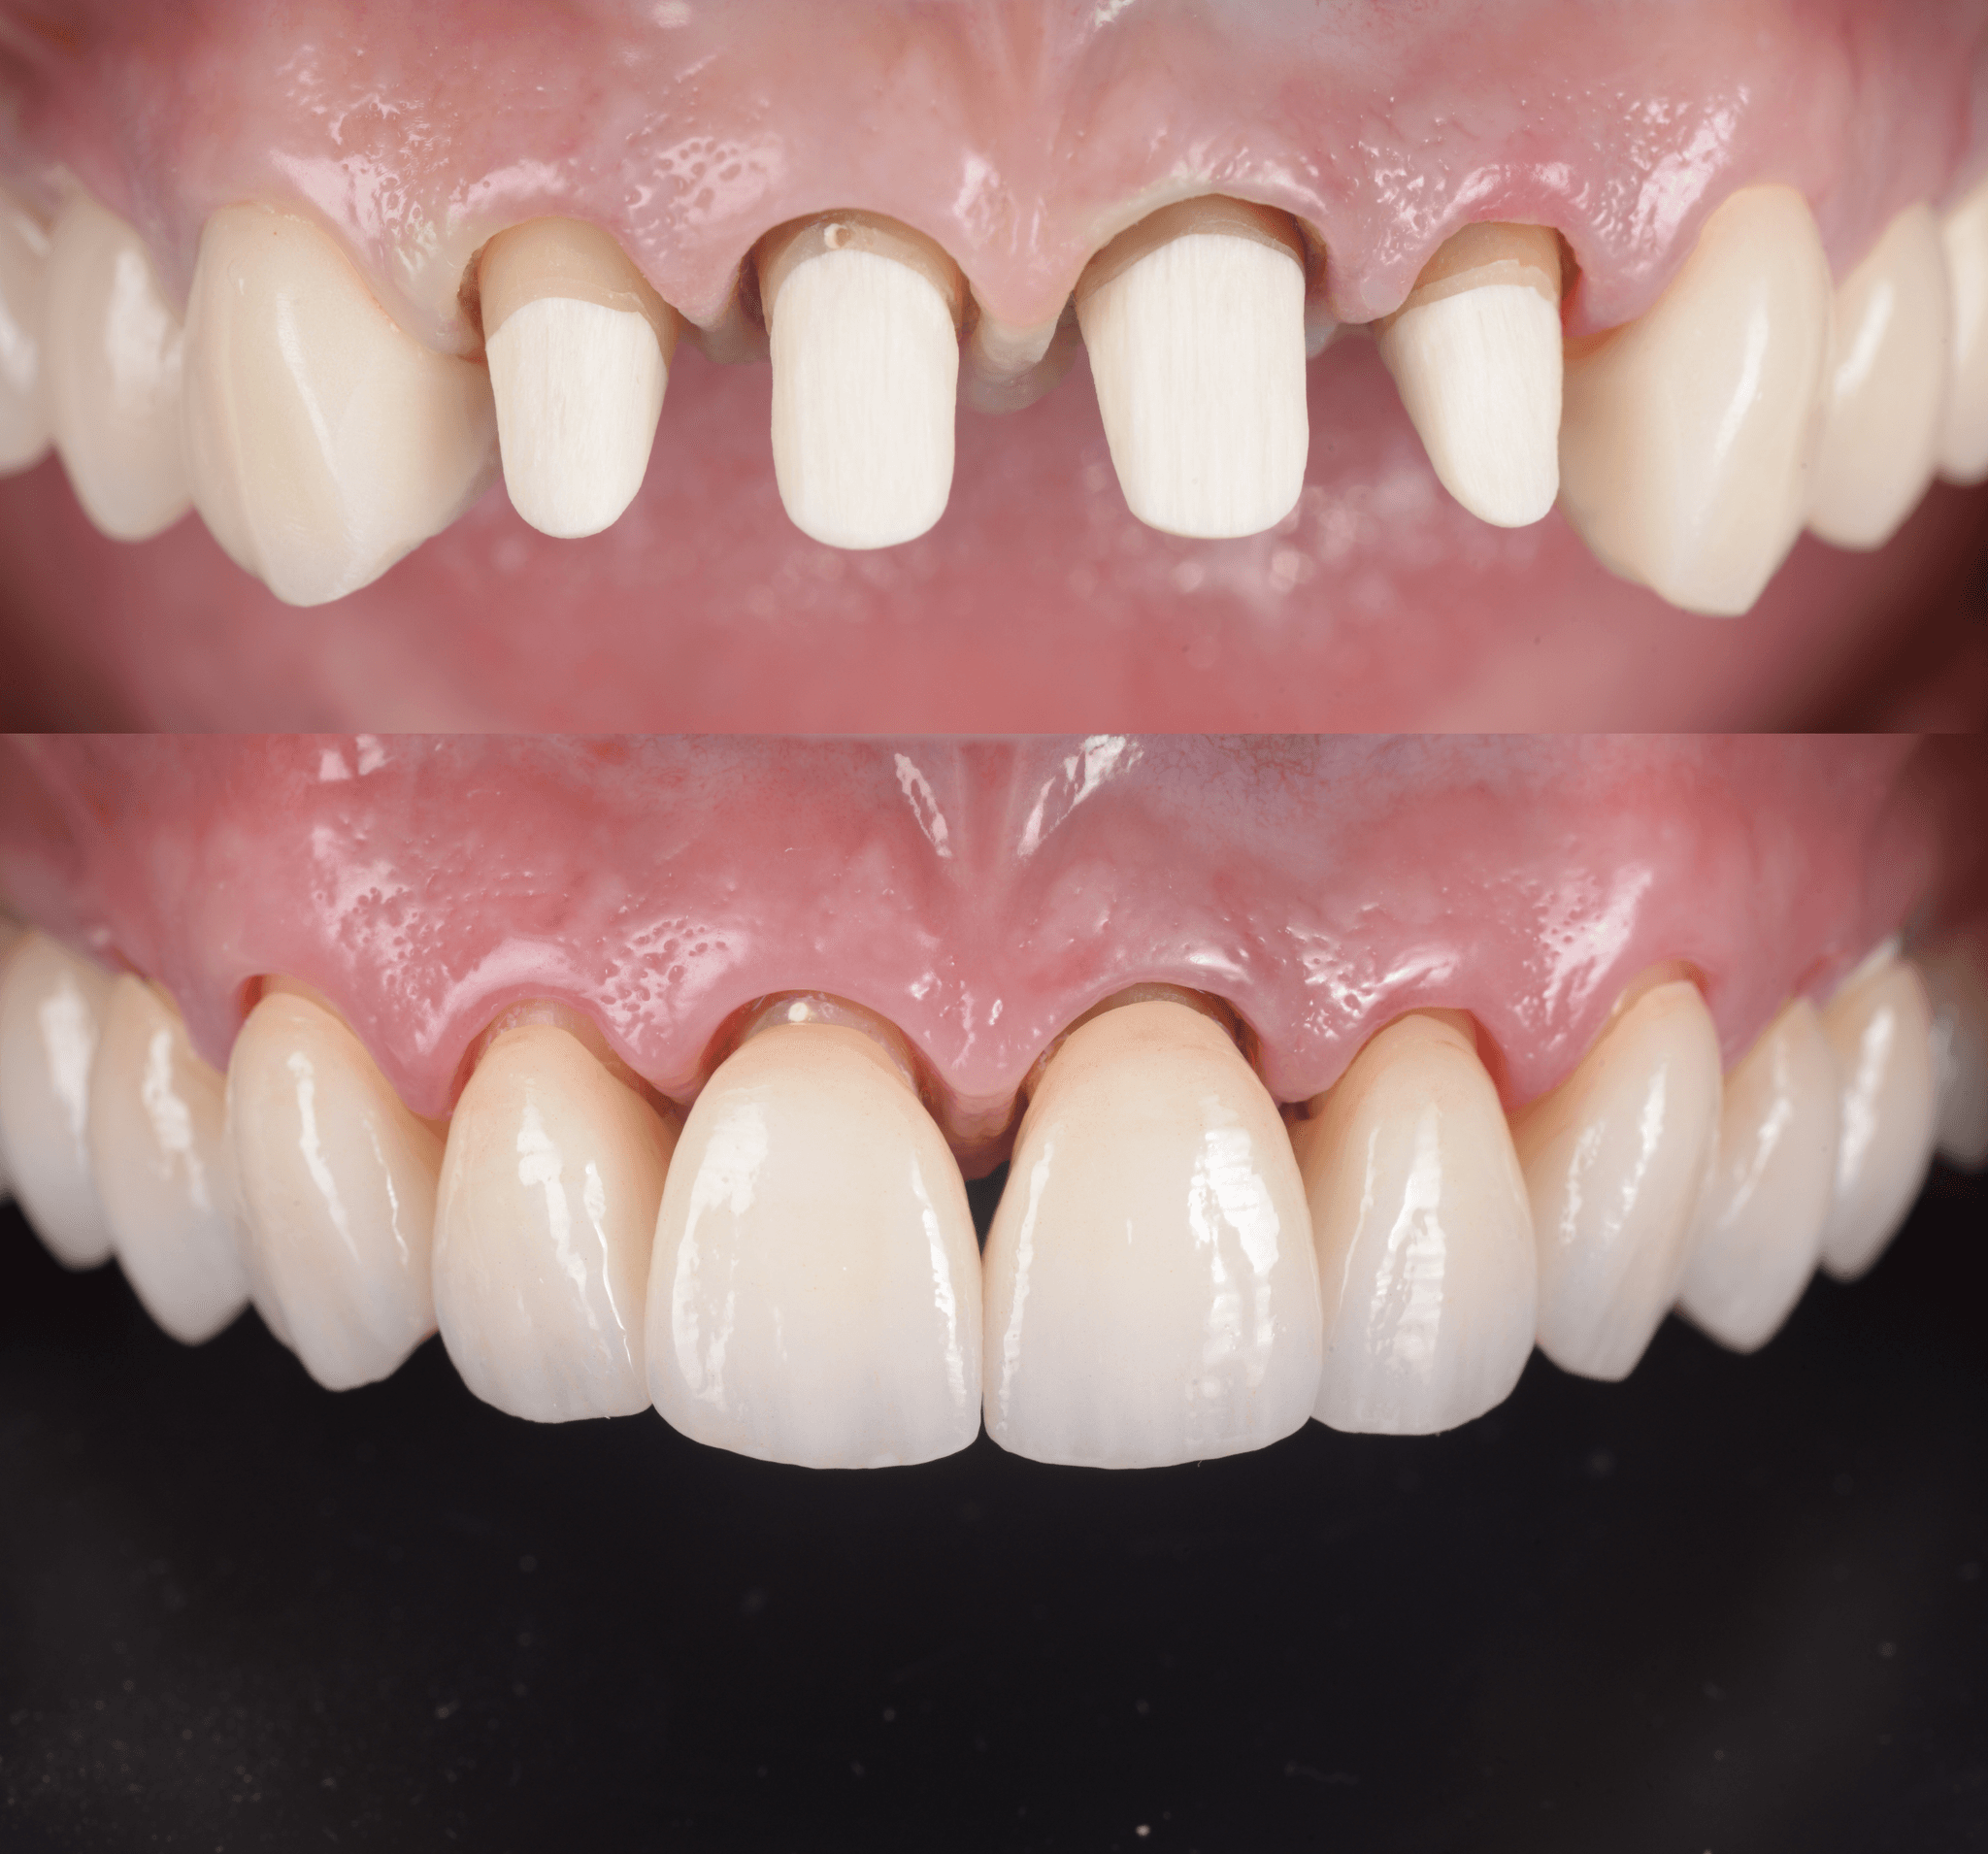

3. Sealing and Restoration Planning

Once the canals are sealed, we assess what kind of restoration is appropriate. In many cases, especially when significant structure remains, a direct composite restoration is sufficient. For severely damaged teeth, we may use a CAD-designed post and core to rebuild internally before placing a crown.

Designed for Restoration, Not Just Removal

Endodontic success isn’t just measured by what’s removed, but by how the tooth performs after. We plan the restoration from the beginning, ensuring that the tooth can function well and support future prosthetic work if needed.

CAD-designed posts. Real-time guidance.

When structural damage requires rebuilding, we don’t rely on standard posts. We use custom-designed posts built from your tooth scan, ensuring optimal fit and stress distribution. This improves retention, reduces fracture risk, and aligns with your final prosthetic plan.